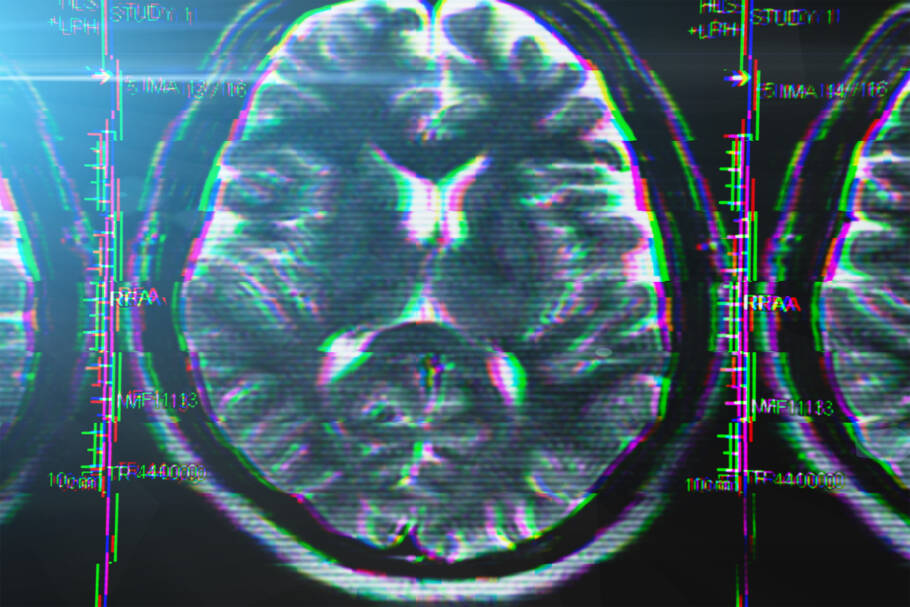

A DFT é um tipo raro de demência que afeta principalmente as regiões frontal e temporal do cérebro, áreas responsáveis pelo comportamento, personalidade, linguagem e tomada de decisões. É diferente do Alzheimer, pois os sintomas iniciais não são de perda de memória, mas sim mudanças profundas no comportamento e na forma como a pessoa interage com o mundo.